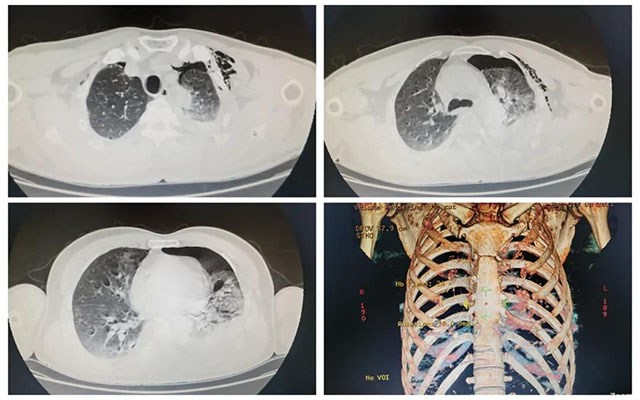

患者刘某某,男,51岁,因车祸致全身多处疼痛,在当地医院就诊,初步检查提示多处肋骨骨折、血气胸、骨盆多发骨折,予初步处理后,紧急送至我院急诊救治。急诊科接诊后,立即启动创伤中心绿色通道,紧急完成CT扫描提示“左侧血气胸、左肺受压60%、左侧胸壁积气、右侧液气胸,胸部多发肋骨骨折、左侧肩胛骨粉碎性骨折、左侧耻骨骨折”等多发创伤,其中,最为危急的是左侧胸腔积血、积气、左肺明显受压,需立即启动手术治疗。

左侧血气胸、胸部肋骨多发骨折CT图像